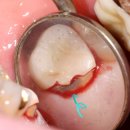

있는 정석적인 치료를 하는 치과의사입니다. 원데이 신경치료로, 하루 만에 자연치아 보존 성공! 세브란스 치과대학병원 치과보존과에서의 긴 신경치료 경험을 살려 당일로 마무리되는 원데이 신경치료를 서둘러서 진행했습니다. 제가 신경치료를 할 때 특히 신경 쓰는 부분은 신경치료를 할 때 오프닝 (치아 내부 진입...

세브란스 출신 대표원장의 고난도 재신경치료/C형근관(2025-07-27 01:56:00)